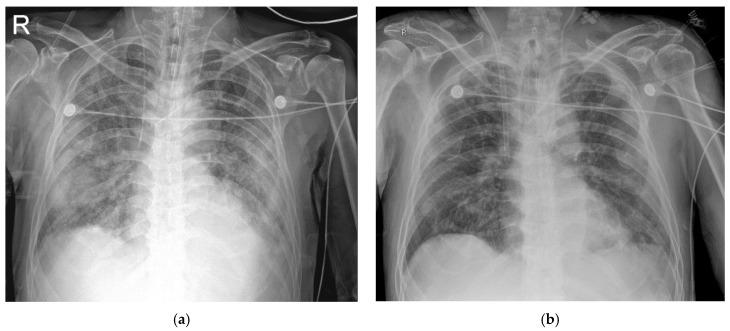

Coronavirus disease (COVID-19) started in Wuhan (China) at the end of 2019, and then increased rapidly. In patients with severe acute respiratory distress syndrome (ARDS) caused by COVID-19, venovenous extracorporeal membrane oxygenation (VV-ECMO) is considered a rescue therapy that provides adequate gas exchange. The way in which mechanical ventilation is applied during VV-ECMO is not clear, however it is associated with prognosis. Currently, the mortality rate of COVID-19 patients that receive VV-ECMO stands at approximately 50%. Here, we report three patients that successfully recovered from COVID-19-induced ARDS after VV-ECMO and implementation of an ultra-protective ventilation. This ventilation strategy involved maintaining a peak inspiratory pressure of ≤20 cmHO and a positive end-expiratory pressure (PEEP) of ≤ 10 cmHO, which are lower values than have been previously reported. Thus, we suggest that this ultra-protective ventilation be considered during VV-ECMO as it minimizes the ventilator-induced lung injury.

Case Report of Patients with Acute Respiratory Distress Syndrome Caused by COVID-19: Successfully Treated by Venovenous Extracorporeal Membrane Oxygenation and an Ultra-Protective Ventilation.